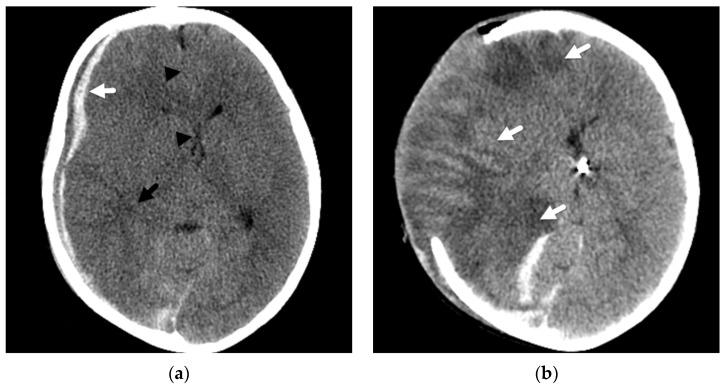

Subdural hemorrhage is a key imaging finding in cases of abusive head trauma and one that many radiologists and radiology trainees become familiar with during their years of training. Although it may prove to be a marker of trauma in a young child or infant that presents without a history of injury, the parenchymal insults in these young patients more often lead to the debilitating and sometimes devastating outcomes observed in this young population. It is important to recognize these patterns of parenchymal injuries and how they may differ from the imaging findings in other cases of traumatic injury in young children. In addition, these parenchymal insults may serve as another significant, distinguishing feature when making the medical diagnosis of abusive head injury while still considering alternative diagnoses, including accidental injury. Therefore, as radiologists, we must strive to look beyond the potential cranial injury or subdural hemorrhage for the sometimes more subtle but significant parenchymal insults in abuse.

硬膜下出血是虐待性头部创伤病例中的一项关键影像学表现,许多放射科医生和放射科实习生在多年培训过程中都对其有所了解。虽然在没有受伤史的幼儿或婴儿中,硬膜下出血可能被证明是创伤的一个标志,但这些年轻患者的脑实质损伤更常导致在这一年轻人群中观察到的使人衰弱甚至有时是毁灭性的后果。认识这些脑实质损伤的模式以及它们与幼儿其他创伤性损伤病例的影像学表现有何不同很重要。此外,在做出虐待性头部损伤的医学诊断时,在仍考虑包括意外伤害在内的其他诊断时,这些脑实质损伤可能是另一个重要的、有区别性的特征。因此,作为放射科医生,我们必须努力超越潜在的颅脑损伤或硬膜下出血,去寻找虐待中有时更细微但却很重要的脑实质损伤。